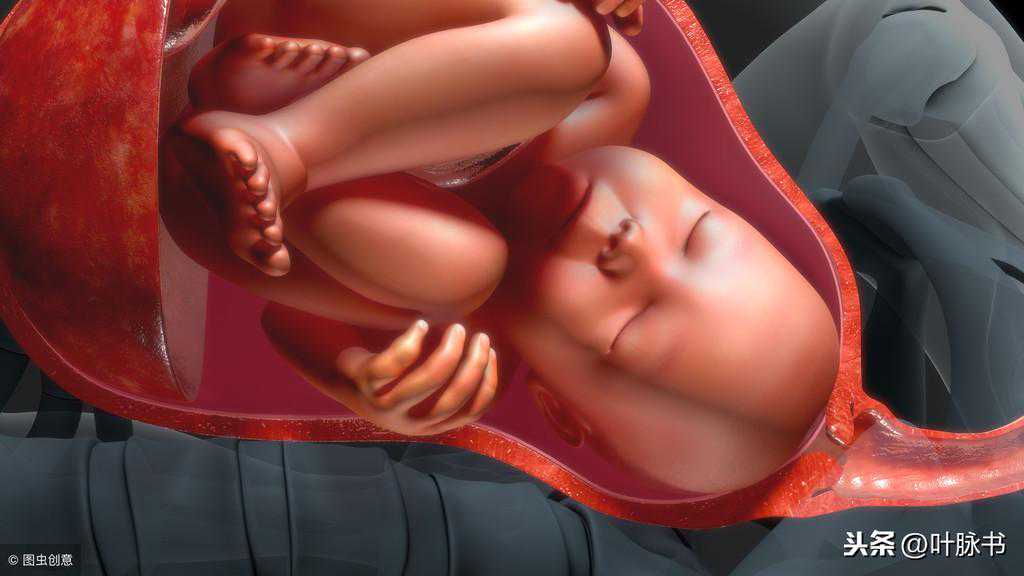

人造子宫人造子宫是试管授精研究带来的一个副产品,研究它的目的同样是为了帮助那些不育夫妇。认为她们小组将在5~10年内培育出活的老鼠子宫,而人体子宫还要等上更长的时间。